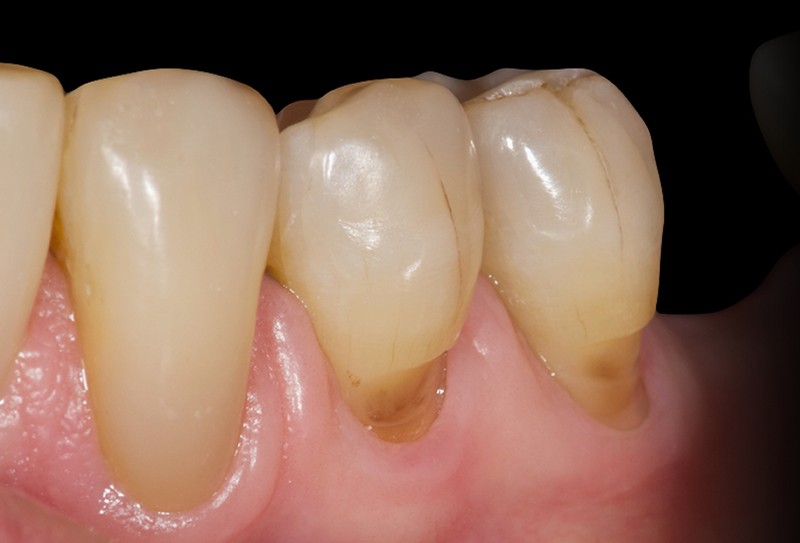

Les lésions cervicales non carieuses (LCNC ; Non-Carious Cervical Lesions, NCCL en anglais) sont des états pathologiques caractérisés par la perte de structure dentaire au niveau de la jonction amélo-cementaire qui ne sont pas liés à la carie dentaire [8] (fig. 1).

Les LCNC sont presque exclusivement situées sur les faces vestibulaires des dents, rarement sur les faces linguales et proximales. Plusieurs études ont montré qu’elles sont plus marquées sur les incisives, les canines et les prémolaires et qu’elles sont plus fréquentes sur le maxillaire qu’à la mandibule [7, 11].

En général, les LCNC varient…